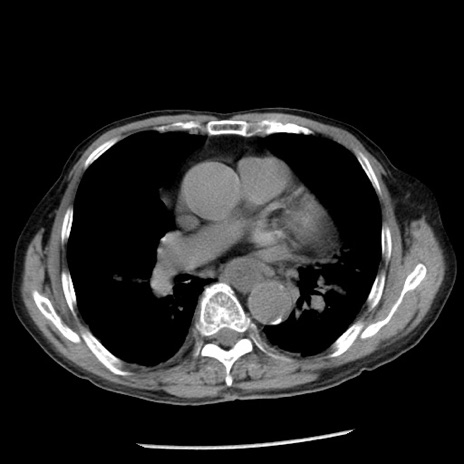

症例26(横断像)

【症例】80歳代男性

【主訴】嘔吐

【現病歴】昨晩2回嘔吐あり、今朝になっても嘔吐あり。来院。

【既往歴】胃潰瘍

【身体所見】意識清明、BT 37.6℃、BP 166/95mmHg、HR 100bpm、SpO2 97%、腹部:平坦・軟、腸蠕動音聴取良好、圧痛なし。

【データ】WBC 21900、CRP 1.46